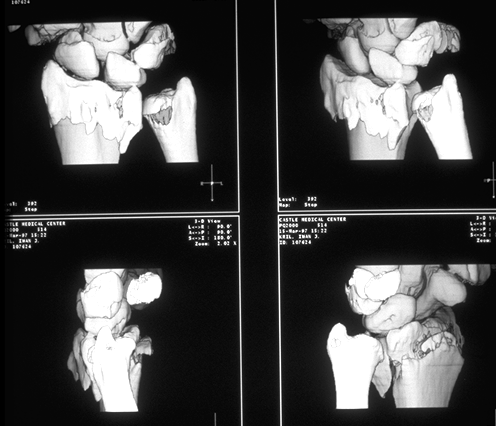

Case 3 CT